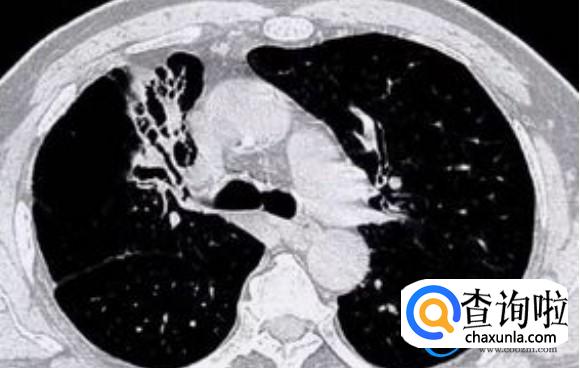

随着疫情政策放开之后,全国上下有众多人士已经感染了新冠,其中有部分患者在感染新冠以后出现了失眠的情况要说失眠,可能是肺部出现了问题,比如失眠是慢性肺病,在晚期经常容易出现的一种状态,这种状态虽说是不健康的状态,但是它会给病人造成严重的影响。

当然患者出现慢性阻肺,产生的失眠跟普通的失眠会有很大的不同,他们所表现的症状是日夜颠倒,白天特别想睡觉,晚上却睡不好,一旦出现这类情况之后,需要及时去医院就诊,避免引发新的问题。

部分患者一觉睡到天亮,属于正常情况,但是有些患者在晚上睡觉时一般到早上3点以后醒来会直接出现睡不着的情况,虽然此时会觉得特别的累,但是想要睡觉却特别的困难,去看中医时,中医认定为肺部出现了问题。

一般凌晨3点以后身体的所有胀气其实是在肺部管理,如果这个时间段中断了睡眠,其实就是肺部产生了问题,一般肺好整个人的呼吸是特别顺畅的,一切都处于健康运作的状态,当然有些人肺部出现了问题,在睡觉时明显产生了异常,在这样的情况下需要及时的去看医生。